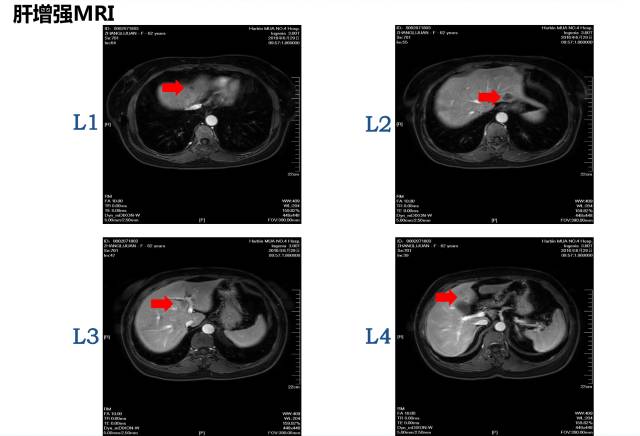

病理:盲肠腺癌肝脏MRI:共8枚病灶

1 2 肝转移病灶

3 右半结肠肿瘤

邢宝才教授:1cm以上的病灶影像学特征较为明显,1cm以下的不明显病灶可以进行超声造影,CT敏感性约为80%,核磁共振(MRI)敏感性约90%多,核磁共振(MRI)+ 普美显敏感性约96~97%。针对小病灶,核磁+普美显的肝胆特异期联合DWI的检测误差较小。术前我们对病灶应进行细致的影像学评估,而判断是否转移应以术后病理结果为准。